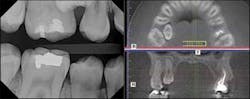

If tooth No. 5 was damaged, we would be better off extracting it and bringing tooth No. 4 into the arch. Cone beam came to the rescue once again by allowing me to fully assess the situation! After viewing the 3-D image, we were able to determine the accurate position of both teeth with respect to each other, and see that there was no damage to the root of No. 5.

With that fact established, I was able to surgically remove No. 4 from the palate. Because of the digital capabilities of both my digital radiography system and my cone beam, I can e-mail or send CDs of the images to referring orthodontists, oral surgeons, or prosthodontists. All of us can share the benefits of this diagnostic tool.

The 3-D image clearly detailed the vessels in the palate, so I had the confidence to perform the surgery to remove tooth No. 4 myself. Now, my patient is doing terrific. I eliminated the cause of a developing problem, probably reducing the length of more comprehensive orthodontic treatment later.